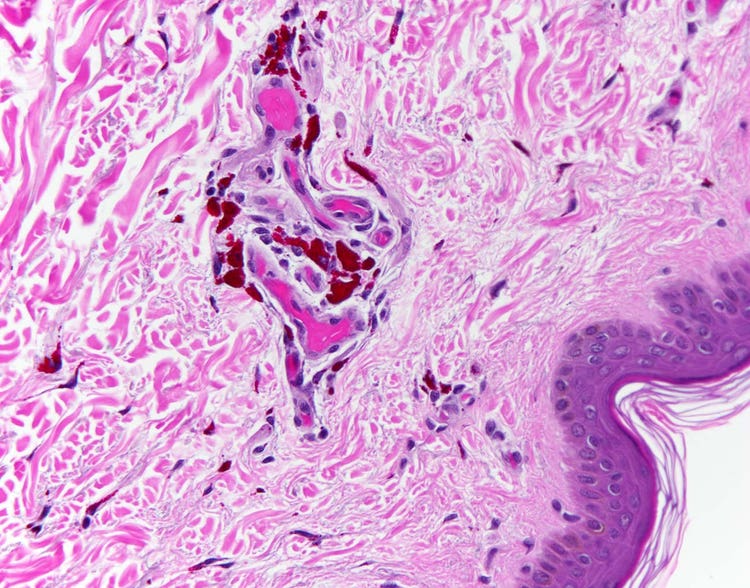

Coupe de peau humaine tatouée. Chaque granule pigmentaire est visible à fort grossissement au niveau du derme, à savoir la couche profonde de la peau. D’autres couleurs de granule pigmentaire sont observables au microscope, comme le noir, le bleu et le doré. Image acquise avec un microscope BX43 d’Olympus équipé d’une caméra DP26. Image reproduite avec l’aimable autorisation de Marianne Hamel.